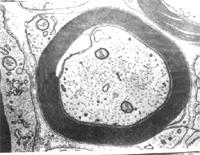

有髓神经纤维描述:神经纤维平行排列成束,在每条神经纤维的中央有轴突,外包雪旺氏细胞形成的髓鞘,神经纤维每隔一定距离有一环状的缩细部称郎飞氏结,此处髓鞘中断,雪旺氏细胞膜直接与轴突相贴。在神经纤维间可看到椭圆形的细胞核,是结缔组织中的成纤维细胞核,染色较深。

有髓神经纤维(myelinated nerve fiber)由轴突(或树突)、髓鞘、神经膜构成。髓鞘(myelin sheath)及神经膜(neurolemma)呈鞘状包裹在轴突的周围。在轴突的起始部无髓鞘包裹,称此部为起始段(initial segment)起始段远侧的轴突部分,髓鞘呈节段包卷轴突,形似藕节,其间断部位,轴膜裸露,,可发生膜电位变化,称此部位为神经纤维节(node of nerve fiber),又称郎飞结(Ranvier node)。两个相邻结之间的一段,称结间体(internode),长约0.5~lmm,它是由一个施万细胞所形成的髓鞘及其周围的神经膜构成。施万细胞核呈长椭圆形,位于髓鞘边缘的少量胞质内。髓鞘主要是由类脂质和蛋白质所组成,称为髓磷脂(myelin)在常规染色标本上,因髓鞘中的类脂被溶解,仅见残存的蛋白质呈网状,称神经角演网(neurokeratin network)。在锇酸浸染标本上,髓鞘呈黑色,其中还可见数个呈漏斗形的斜裂,称髓鞘切迹(incisure of myelin)或施-兰切迹(Schmidt-Lanterman incisure)。电镜下,髓鞘为明暗相间的同心圆板层排列。髓鞘有保护和绝缘作用,可防 止神经冲动的扩散。

(1)周围神经系统的有髓神经纤维:这种神经纤维的轴突,除起始段和终末外均包有髓鞘。髓鞘分成许多节段,各节段间的缩窄部称郎氏结(Ranvier node)。轴突的侧支均自郎氏结处发出。相邻两个郎氏结之间的一段称结间体(internode)。轴突越粗,其髓鞘也越厚,结间体也越长。每一结间体的髓鞘是由一个施万细胞的胞膜融合,并呈同心圆状包卷轴突而形成的,电镜下呈明暗相间的同心状板层。髓鞘的化学成分主要是类脂和蛋白质,称髓磷脂(myelin)。髓磷脂中类脂含量很高,约占80%,故新鲜髓鞘呈闪亮的白色,但在常规染色标本上,因类脂被溶解,仅见残留的网状蛋白质。若标本用锇酸固定和染色,髓磷脂保存,髓鞘呈黑色,在其纵切面上常见一些漏斗型的斜裂,称施-兰切迹(Schmidt-Lantermann incisure)。

施万细胞的胞核呈长卵圆形,其长轴与轴突平行,核周有少量胞质。由于施万细胞包在轴突的外面,故又称神经膜细胞(neurilemmal cell),它的外面包有一层基膜。施万细胞最外面的一层胞膜与基膜一起往往又称神经膜(neurilemma),光镜下可见此膜。